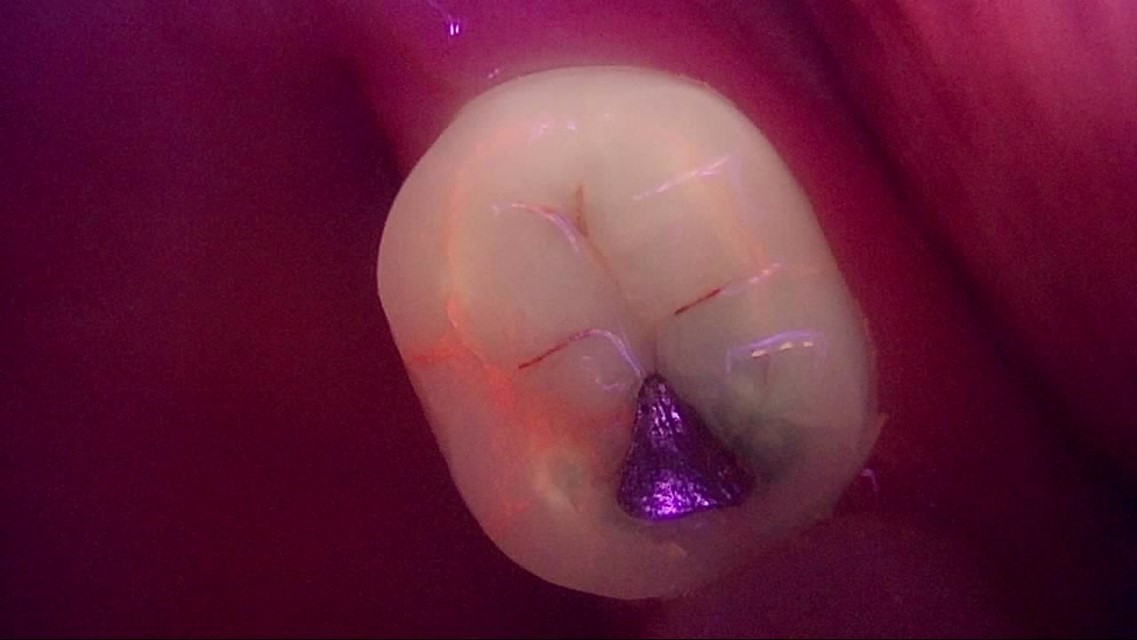

Crack

큐레이캠프로, 큐레이펜씨